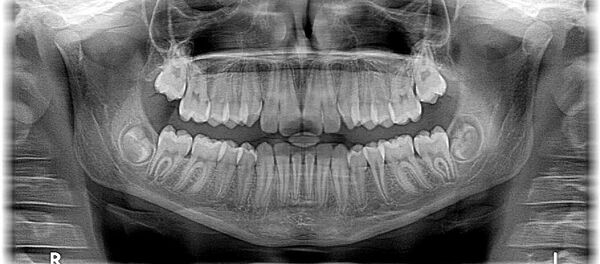

Les scientifiques ont confirmé l’authenticité des dents et du crâne qu’ils ont pu examiner sur autorisation des archives d’État russes et du Service fédéral de sécurité (FSB).

Selon l’expertise, la morphologie du crâne conservé à Moscou correspond à des radiographies du crâne d’Hitler réalisées en 1944, un an avant sa mort.

«Les dents sont authentiques, il n’y a aucun doute possible. Notre étude prouve bien que Hitler est mort en 1945», a ajouté M.Charlier.

Les spécialistes avaient du mal à définir si la mort du dictateur avait été causée par du cyanure ou une balle qu’il s’est tiré dans la tête. L’examen des ossements a permis de découvrir des traces de poison sur les dents et les prothèses dentaires, ainsi qu’un trou sur le côté gauche du crâne. Cela permet de supposer qu’Hitler s’est suicidé en prenant une ampoule de cyanure, mais aussi en se tirant une balle dans la tête.

Mais les dents ne portent aucune trace de poudre, ce qui exclut un tir dans la bouche, et fait plutôt penser à un tir dans le cou ou dans la tempe, d’après le scientifique.